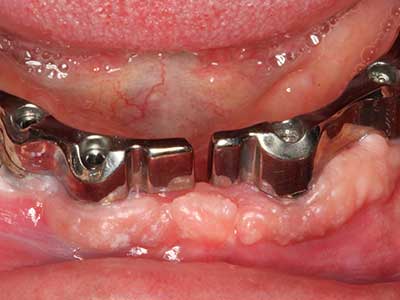

Piezo surgery has additional advantages when harvesting bone blocks. In addition to the high precision with osteotomy described above, the use of the thin saw tips specifically minimizes loss of material. Greater loss of material during harvesting can be expected with the thicker instrument tips, particularly when using Lindemann drills (Lakshmiganthan, Gokulanathan et al. 2012). The basal separation, which is necessary particularly for retromolar block transplants, is simplified by specially designed rectangular saws, with the result that piezo surgery is viewed as a precise, simple and safe procedure for harvesting retromolar bone blocks (Happe 2007) (Fig. 1-12).